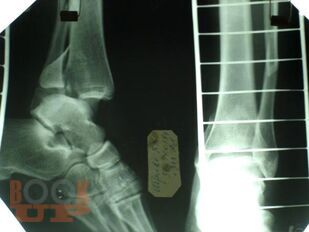

Учебно-методическое пособие содержит необходимую информацию для врачей по вопросам профилактики и лечения последствий тяжелых повреждений области голеностопного сустава. В Пособии представлены условия развития тяжелых статико-динамических осложнений при травмах голеностопного сустава, особенности осложнений при последствиях переломов дистального суставного отдела костей голени. Особое внимание уделено механизму развития посттравматического плоскостопия при повреждениях области голеностопного сустава.

В пособии обобщен более, чем 30-летний опыт лечения пациентов с последствиями тяжелых повреждений области голеностопного сустава.